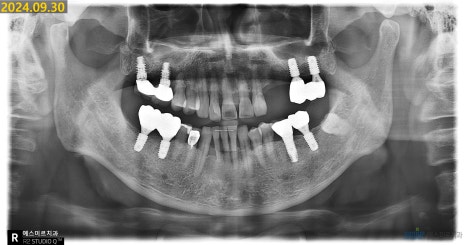

✨ 이번 치료는

염증이 있던 기존 임플란트를 제거하고,

뼈이식과 골유도 재생술을 동반한

임플란트 재식립까지

잘 마무리되었습니다.

(※ 환자 동의하에 제공된 이미지입니다)

환자분은 임플란트 치료를 모두 마무리하셨고

정기 검진을 통해 상태를 꾸준히 점검해드릴 예정입니다 😊